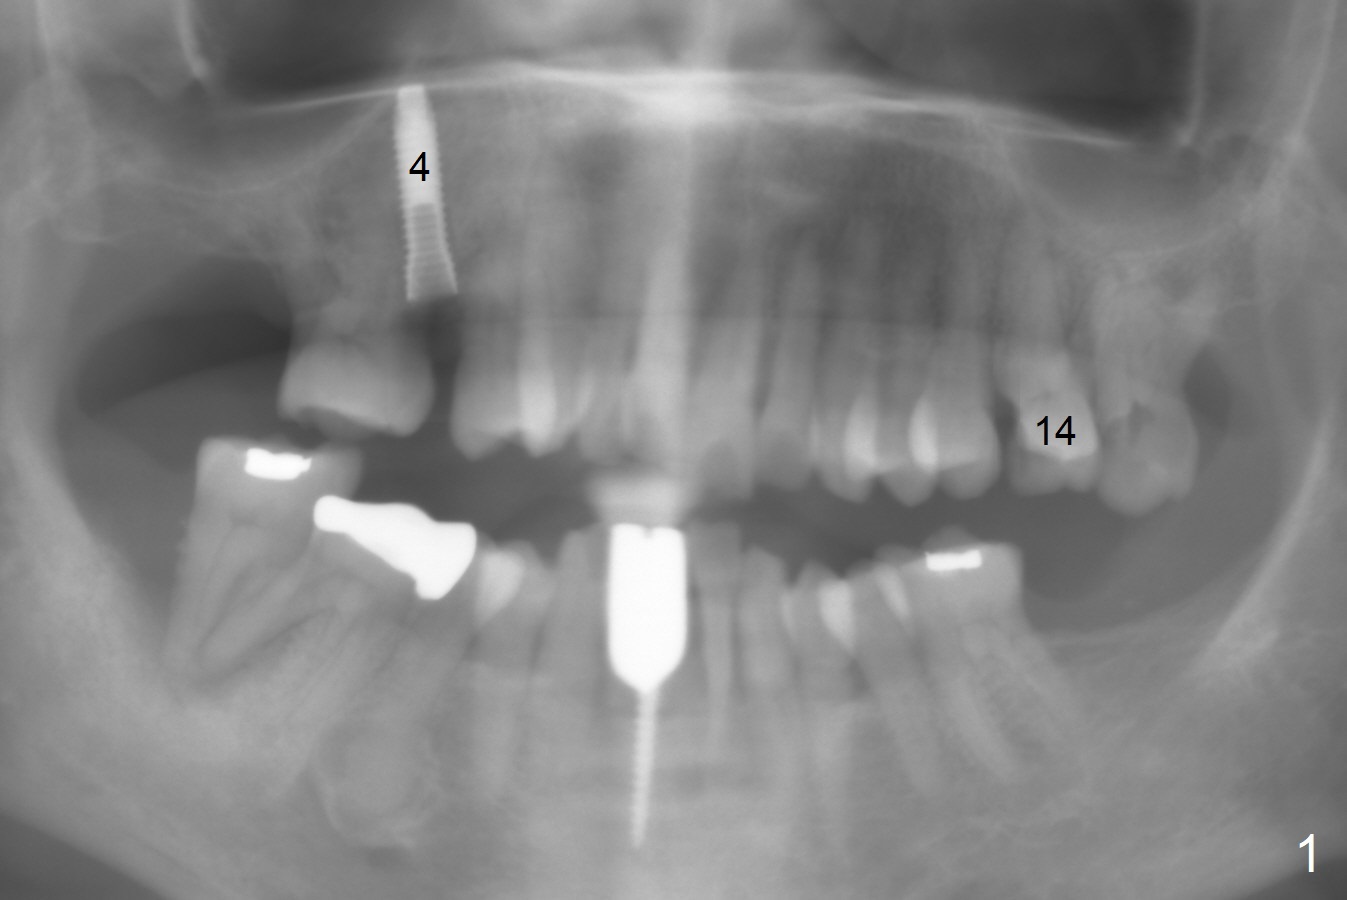

A 65-year-old woman cracks the tooth #14 prior to #4 implant (Fig.1). The height of the septum is ~ 10 mm; initial osteotomy depth will be 8.5 mm; 1-2 mm from the sinus floor. While increasing the drill size, check whether there is perforation on the side of the osteotomy apically. Since the patient is small, start low dose of X-ray.